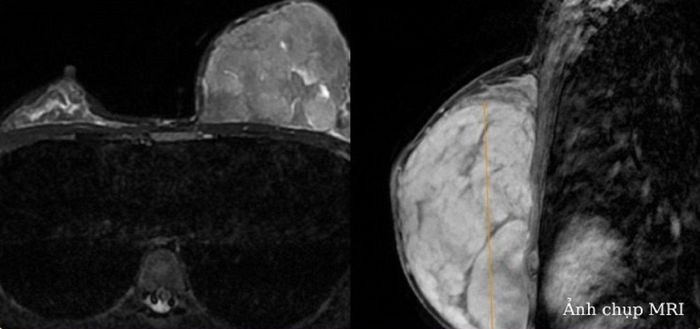

Quá tŕnh siêu âm vú, bác sĩ nhận thấy h́nh ảnh tăng âm, tăng kích thước tuyến vú trái. Chụp MRI tuyến vú thấy khối u lớn nhu mô vú trái, không xân lấn thành ngực, kích thước 124x87x64 mm.